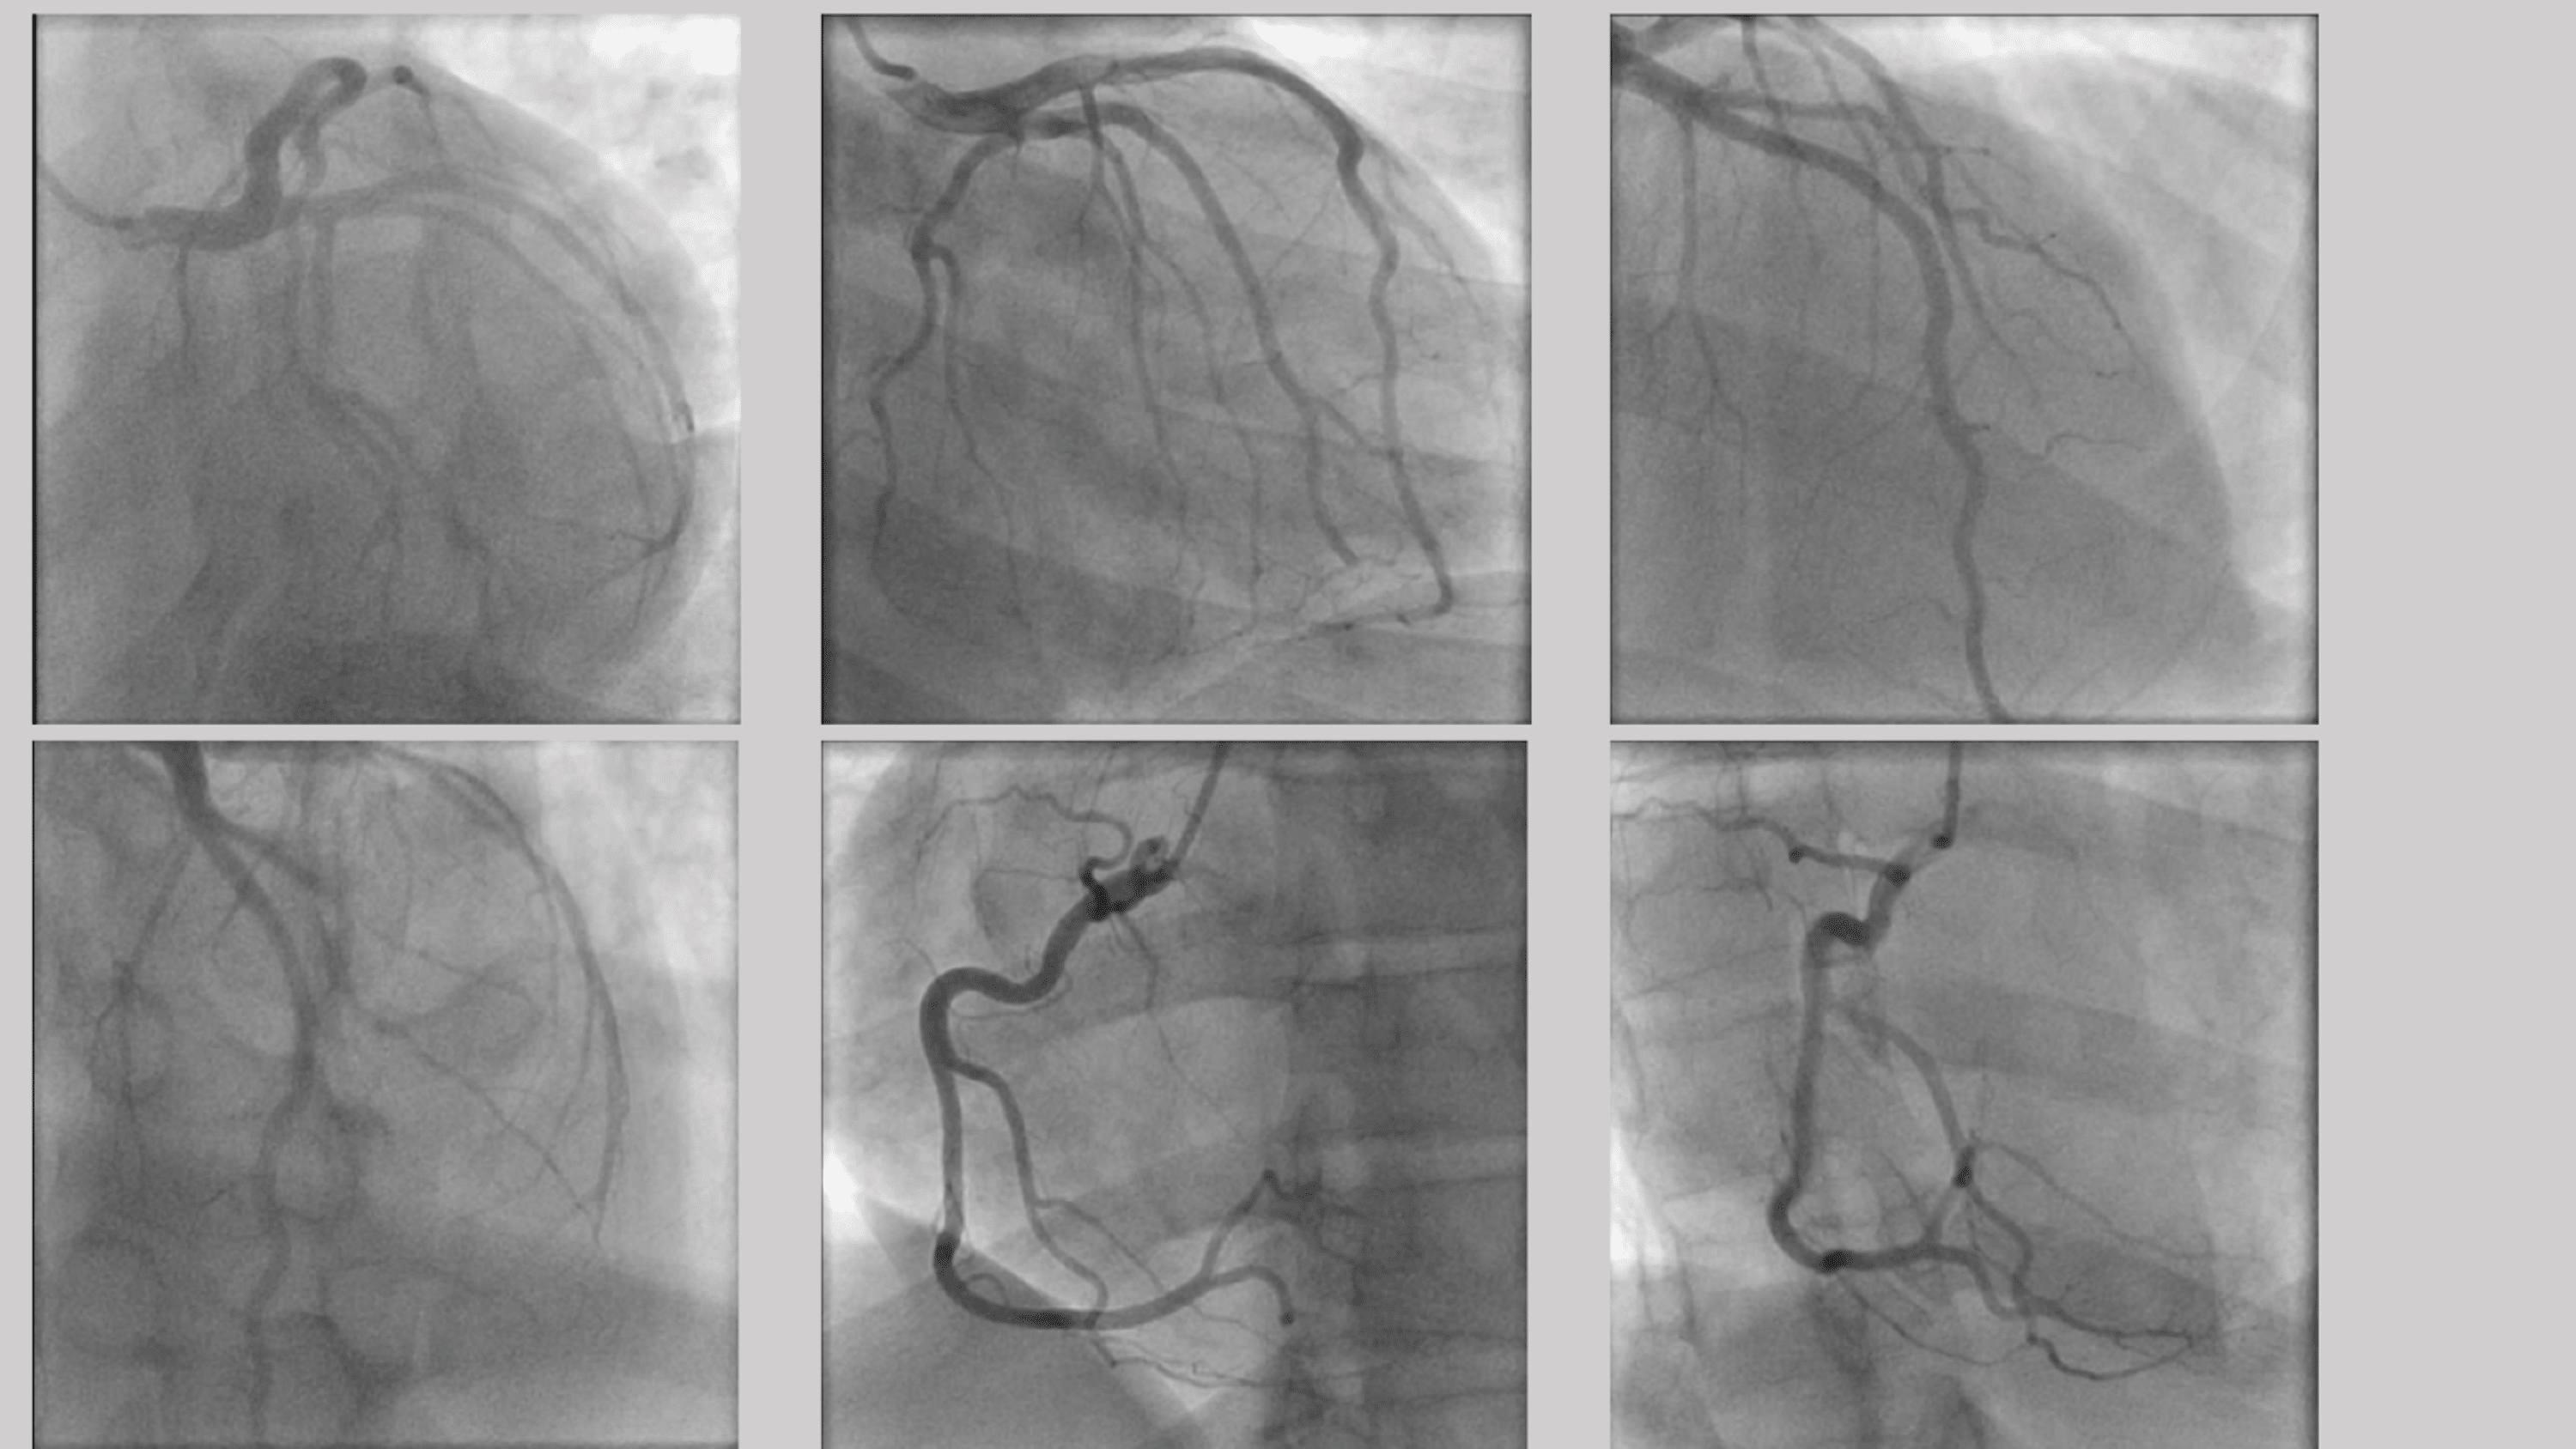

Radial Cardiac Catheter